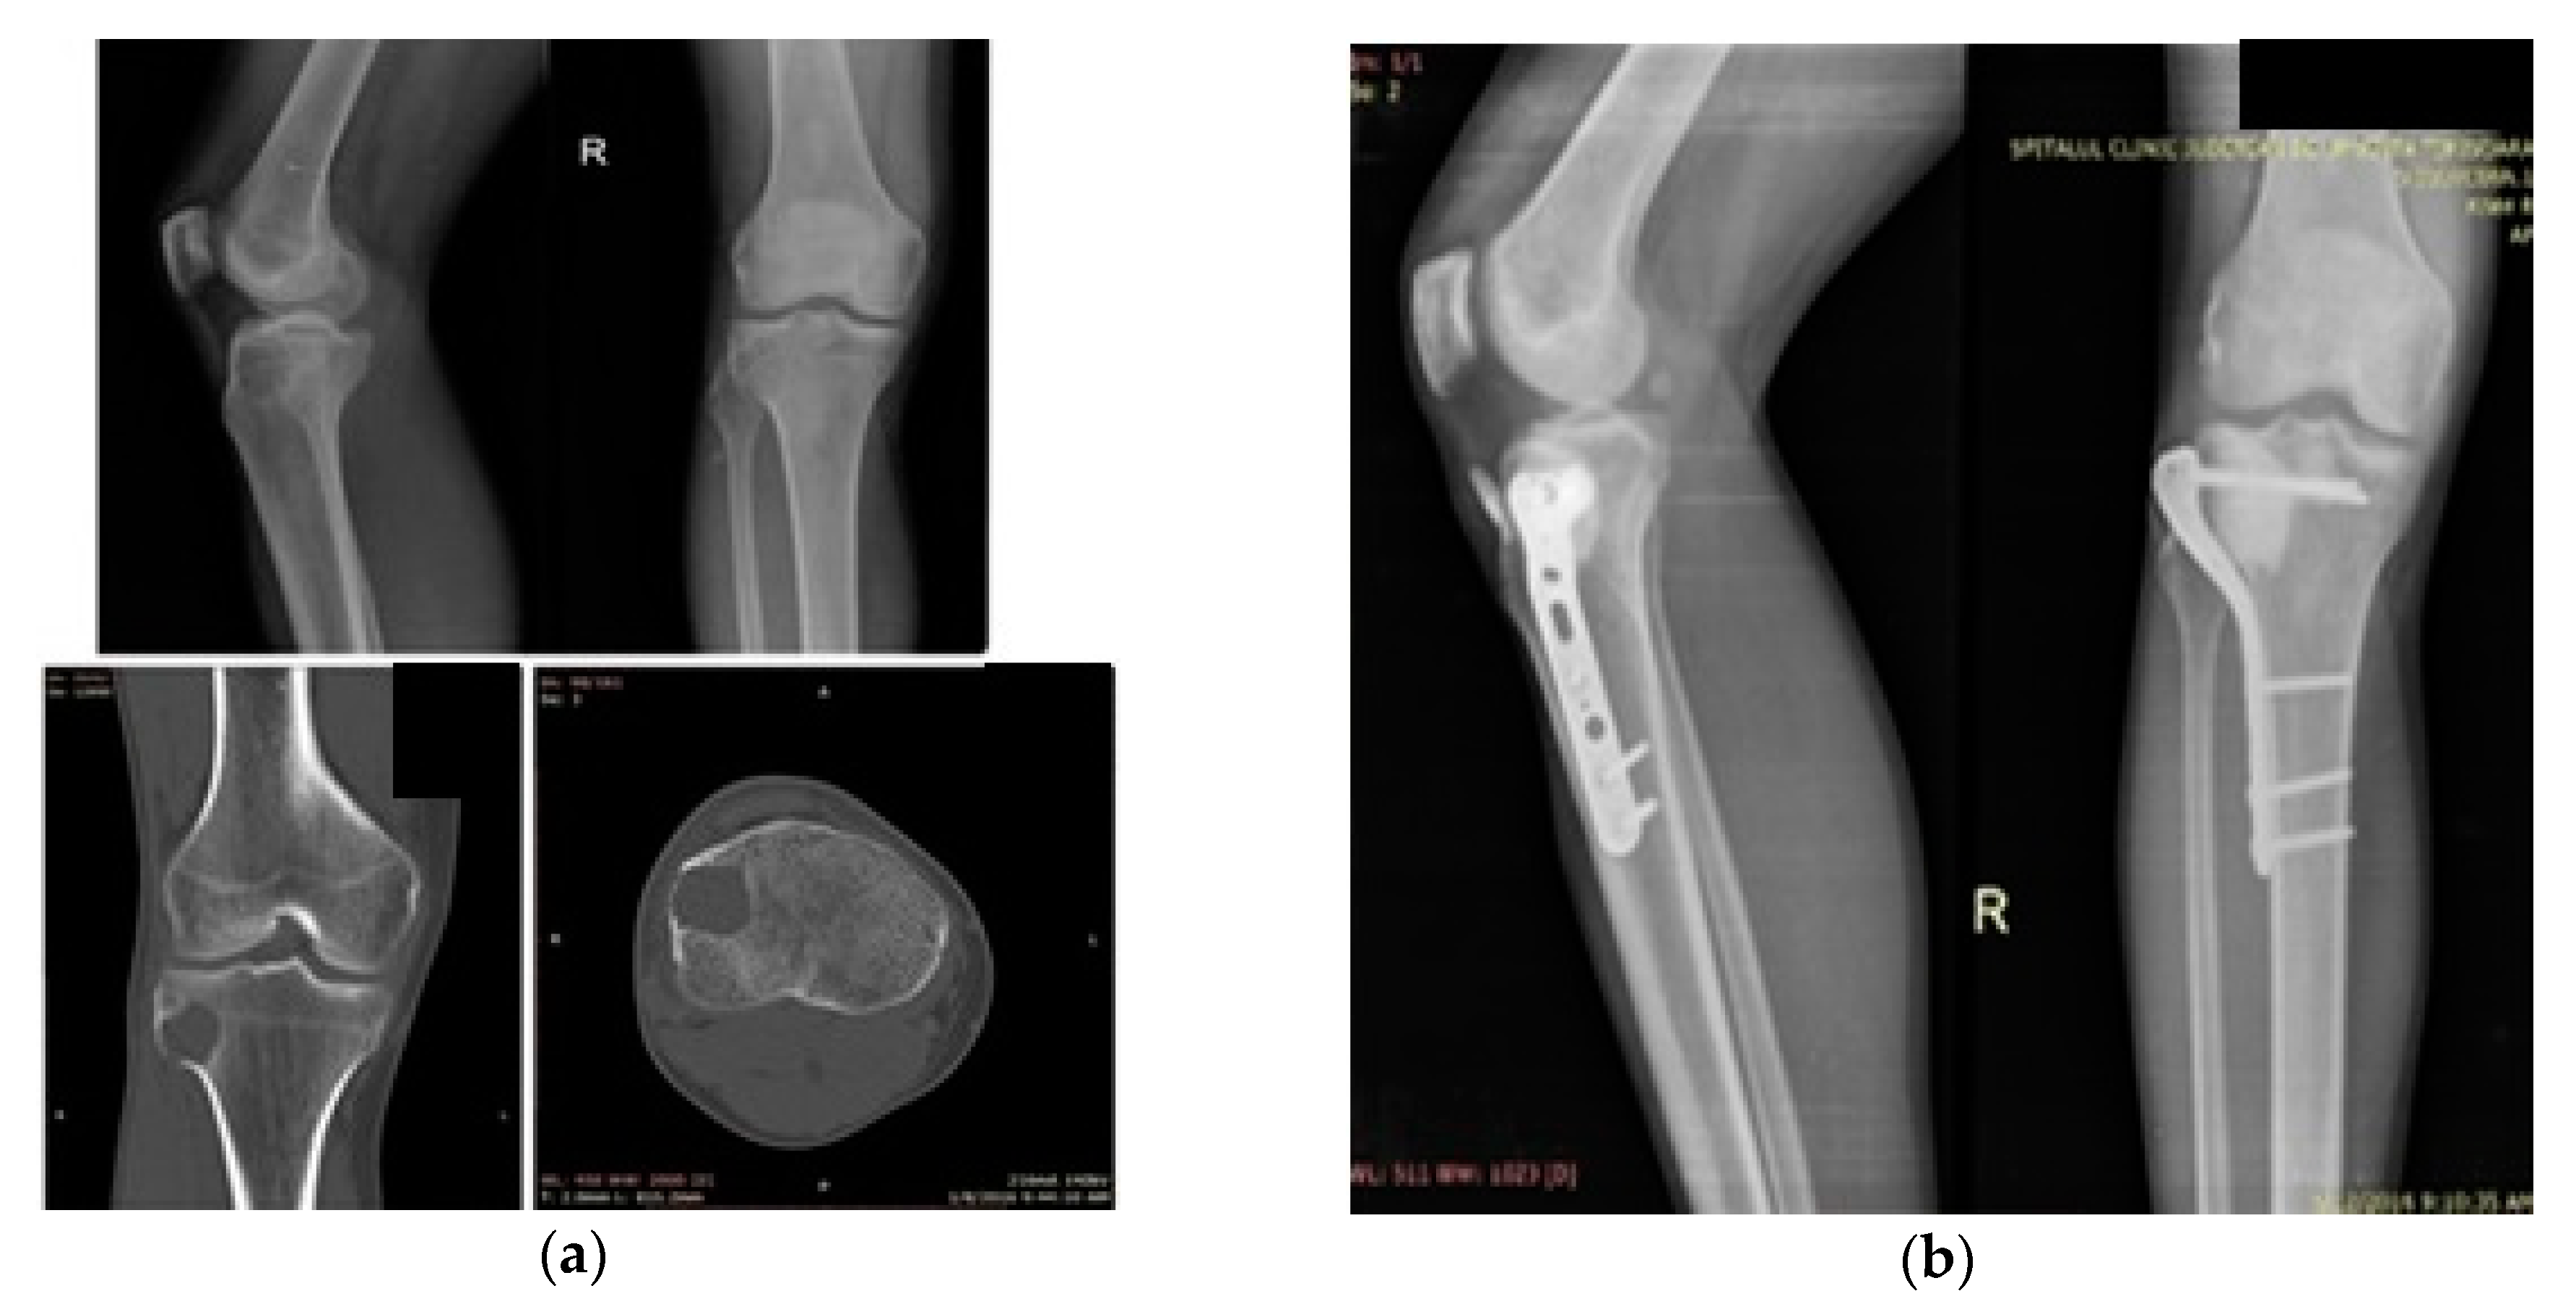

The first case was a 41-year-old male patient with a GCT of proximal tibia with mild pain in the proximal calf. X-ray examination revealed an osteolytic tumor of the anterolateral proximal tibia. The CT scan confirmed the location of the tumor without interruption of the cortices. Location, age and the imaging data raised the suspicion of a GCT of the proximal tibia, confirmed after bone needle biopsy (Figure 1a).

Case 1: 41-year-old male. (a) Giant cell tumor (GCT) of the proximal tibia, preoperative X-ray and CT scan; (b) X-ray (lateral and AP) two years after surgery with no signs of recurrence.

Surgical treatment was performed under tourniquet use, as was previously mentioned. An anterolateral approach of the proximal tibia was preferred. Following excision of the GCT, a motorized high-speed ball-tipped drill burr was used for uniformization of the walls of the tumoral cavity. Sealing of the tumoral field was achieved by using Gelfoam and gauze soaked in warmed saline. LN was delivered using a specially designed pump. The freeze–thaw cycle was repeated two times. The resulting cavity was filled with bone cement without antibiotic load and reinforced with a 4.5 mm six-screw locking compression plate (LCP) Sutures were removed at 14 days with no signs of skin necrosis. Partial weight bearing on the affected limb was recommended for three weeks followed by total weight bearing being tolerated afterwards. Follow-up was performed at six weeks, three months, six months and once per year afterwards.

The two-year follow-up revealed no signs of recurrence, with full range of motion of the knee joint and absence of pain. The postoperative X-ray (Figure 1b) reveals a small amount of bone cement at the insertion of the patellar tendon, with no functional impairment or residual pain and an IKDC (International Knee Documentation Comitee) functional score of 96.